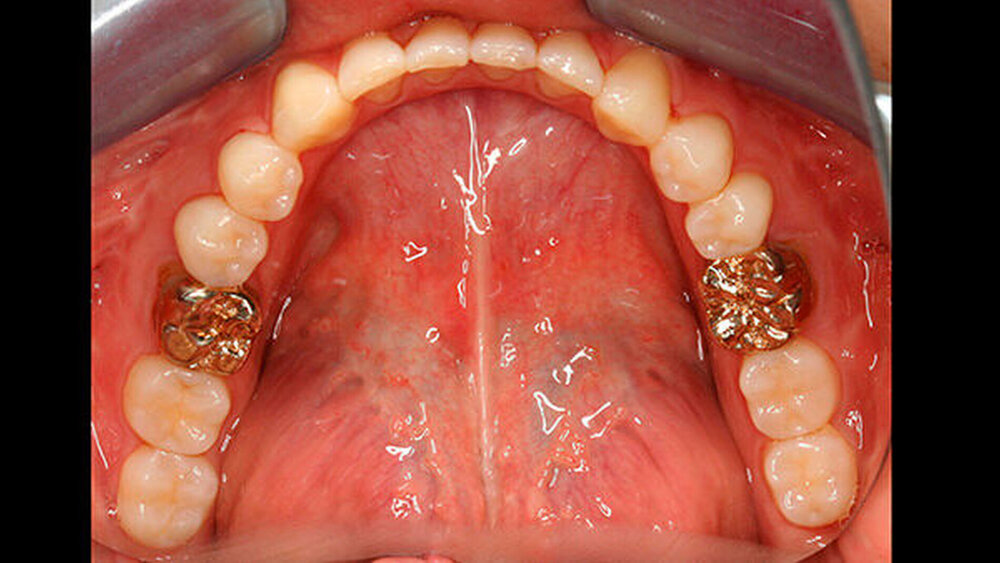

Bisher war die Patientin größtenteils mit provisorischen Maßnahmen behandelt worden. Eine Ausnahme bildeten hier die Sechsjahrmolaren, die ihrzufolge sehr zeitnah nach vollständigem Durchbruch mit Goldteil- beziehungsweise -vollkronen versorgt wurden. Im Oberkiefer wurden später auch für die zweiten bleibenden Molaren Vollkronen gewählt (Abbildungen 1 und 2).

Abbildung 1 gibt einen guten Überblick darüber, dass teils mehrere Restaurationen pro Zahn durchgeführt wurden und die dazwischen verbliebenen Bereiche aus Zahnschmelz oft nur gering waren (insbesondere an den Frontzähnen). Gleichzeitig zeigt aber auch der Vergleich der kontralateralen Prämolaren, wie anfällig dieser verbliebene Schmelz für Abplatzungen war. Im Unterkiefer ist gerade an Zahn 37 deutlich zu erkennen, wie großflächig die Schmelzverluste sein können, wenn auch die Restauration nicht mehr intakt oder vorhanden ist.

Zudem kann es immer wieder zu Abplatzungen des verbliebenen Schmelzes kommen, so dass der entsprechende Zahn eine neue Restauration benötigt, oder die schon vorhandene ausgedehnt werden muss (siehe auch Abbildungen 1 bis 3) [Crawford et al., 2007].